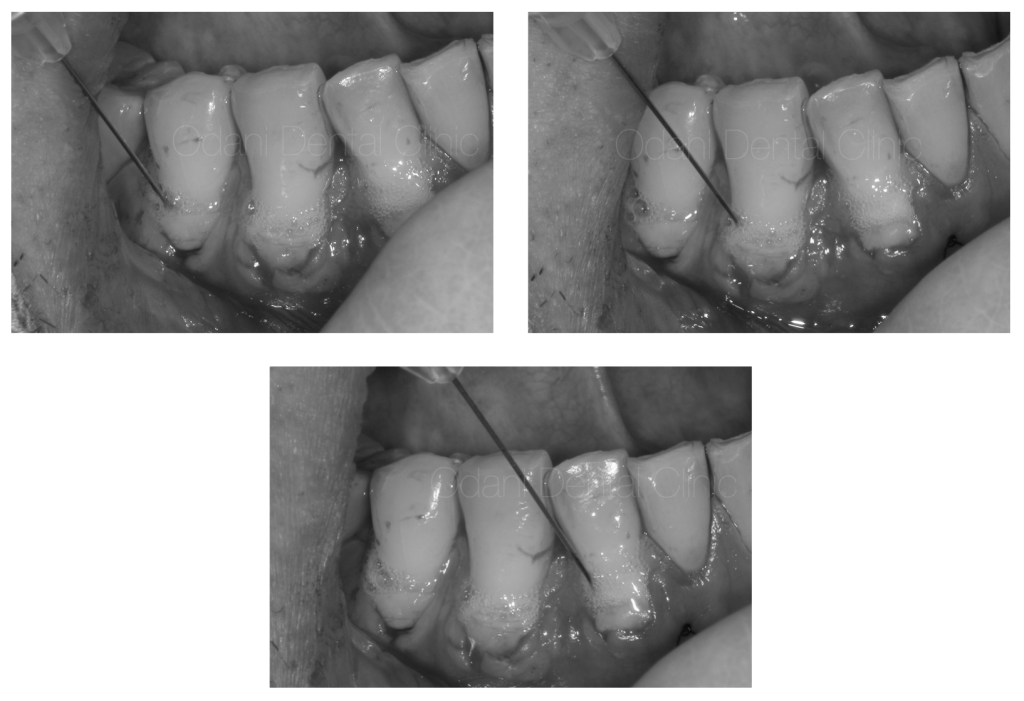

歯周形成外科「根面被覆術」

採取した歯ぐきを調整し(左)、元々の歯ぐきの中に滑り込ませてはさみ込んだ状態(右)です。

移植した歯ぐきと元々の歯ぐきを糸で固定した状態です。